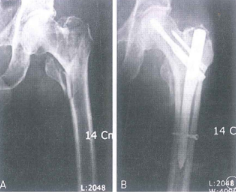

Hình 6.4. Gãy phức tạp dưới mấu chuyển nhiều mảnh rời

Hình 6.9. Gãy phức tạp khối mấu chuyển thân xương- phẫu thuật mổ mở sử dụng đinh nội tuỷ đầu trên xương đùi

Hình 6.9a: Nẹp đầu trên xương đùi với gãy phức tạp DMC và thân xương đùi sau 10 tháng

Hình 6.9b: Nép góc 95 độ điều trị gãy DMC, có ghép xương vào thành sau trong 1 năm